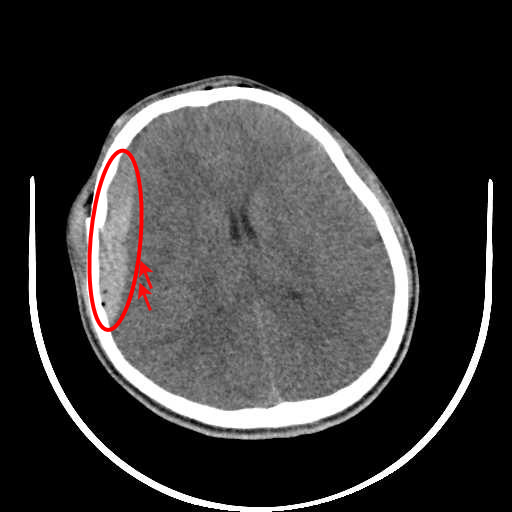

Figure 1: Illustrative examples of different types of brain hemorrhages in CT scans. The hemorrhagic regions are highlighted in red. (a) IPH, (b) IVH, (c) EDH, (d) SAH, (e) SDH.

The dataset used in this study was collected from two medical centers in Tehran, Iran: Rasoul Akram Hospital and Firouzabadi Hospital, over a period spanning 2018 to 2024. All CT scans were manually labeled hierarchically by two board-certified neurosurgeons to ensure accurate classification of ICH subtypes. The labeling process involved an initial annotation by one neurosurgeon, followed by validation and verification by a second expert to minimize errors and inconsistencies. Fig. 1 illustrates representative examples of different ICH subtypes in brain CT scans. The hemorrhagic regions are highlighted in red for better visualization. These annotated examples provide insight into the distinct imaging characteristics of each hemorrhage type, emphasizing the variability in their locations and appearances within the brain. The study received ethical approval, and data collection was conducted in compliance with institutional review board (IRB) regulations and the Declaration of Helsinki, ensuring patient confidentiality and adherence to ethical standards.